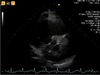

20.2 A 34-year-old woman with cystic fibrosis has had a recent transthoracic echocardiogram to evaluate pulmonary pressure and suitability for lung transplantation. Below is a continuous wave Doppler trace through the tricuspid valve. Her central venous pressure is 5 mmHg. Her estimated right ventricular systolic pressure (RVSP) is (Echocardiography doppler trace shown)

REpeat